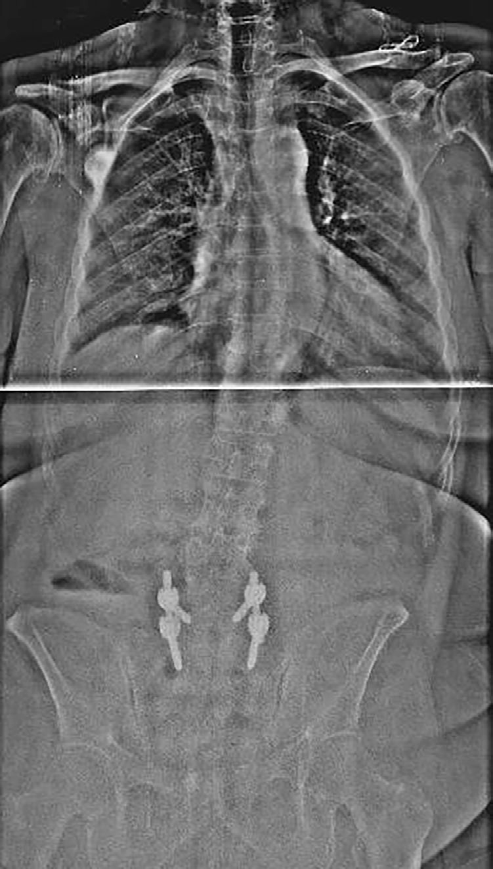

Paciente intervenida de fusión espinal desde T4 hasta hueso ilíaco, además de laminectomía y artrodesis circunferencial TLIF en L3-L4 y L4-L5, por desequilibrio sagital que condicionaba incapacidad a la bipedestación, pérdida de fuerza y disestesias en miembro inferior izquierdo (MII). En el postoperatorio inmediato presenta incapacidad para extender la rodilla izquierda. La neuromonitorización intraquirúrgica (IOM) con potenciales evocados somatosensoriales (SSEP) y potenciales evocados motores (MEP) solo mostraron ligera latencia alargada en SSEPs de lado derecho.

- TC: estenosis foraminal bilateral de T8, ligera medialización de tornillo L3 sin invadir canal medular.

Plejía L3 postquirúrgica.